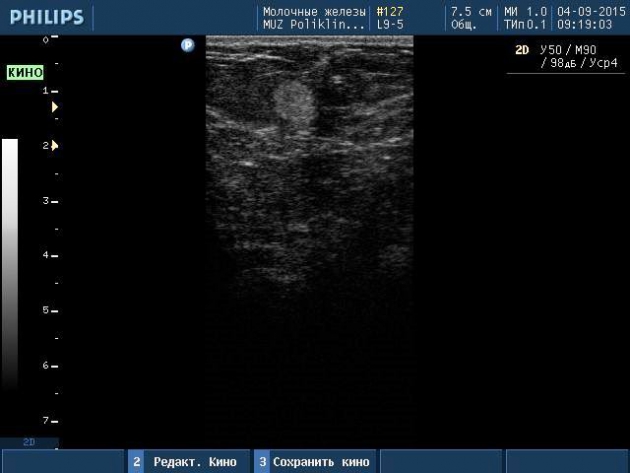

Заранее прошу прощения, если данный вопрос уже обсуждался. Увы. не нашла. Периодически при обследовании молочных желез женщин в постменопаузе в жировых дольках встречаются округлые аваскулярные участки повышенной эхогенности. Где-то пишут, что это зоны стеатонекроза, где-то, что липомы.Сама работаю меньше года, прошу вашего совета))) спасибо!

Стеатонекроз.